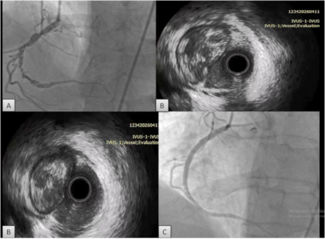

We engaged the RCA again with an 8 Fr JR4 guide and rewired into the acute marginal branch distal to the CTO and into the distal RCA using the same "hairpin wire" technique. We once again encountered significant difficulty delivering equipment to the distal RCA. Several 1.5 mm balloons could not cross. We were finally able to advance a Corsair catheter (Asahi Intecc) (arrow, Figure 2B) to the distal RCA using an anchor balloon technique with a 2.5 mm balloon into a small proximal RCA conus branch (arrowhead, Figure 2B). The Whisper wire (Abbott Vascular) was exchanged for an Ironman wire (Abbott Vascular, arrowhead, Figure 2C), which enabled sequential delivery of 2.0, 2.5, and 3.0 mm balloons and predilation of the entire proximal, mid, and distal RCA. We were then able to deliver three 3.0 mm x 28 mm Xience V everolimus-eluting stents (Abbott Vascular) using a Guideliner catheter (Vascular Solutions, arrow, Figure 2C) for extra guide support. The stents were postdilated with a 3.5 mm non-compliant balloon, providing an excellent final angiographic result (Figure 2D), as confirmed by intravascular ultrasonography. The total fluoroscopy time and air kerma radiation dose were 39.2 minutes and 7.4 Gray, respectively, and 358 mL of contrast were administered. At 1-month follow-up the patient was angina-free and had significantly increased his daily activities.

We engaged the RCA again with an 8 Fr JR4 guide and rewired into the acute marginal branch distal to the CTO and into the distal RCA using the same "hairpin wire" technique. We once again encountered significant difficulty delivering equipment to the distal RCA. Several 1.5 mm balloons could not cross. We were finally able to advance a Corsair catheter (Asahi Intecc) (arrow, Figure 2B) to the distal RCA using an anchor balloon technique with a 2.5 mm balloon into a small proximal RCA conus branch (arrowhead, Figure 2B). The Whisper wire (Abbott Vascular) was exchanged for an Ironman wire (Abbott Vascular, arrowhead, Figure 2C), which enabled sequential delivery of 2.0, 2.5, and 3.0 mm balloons and predilation of the entire proximal, mid, and distal RCA. We were then able to deliver three 3.0 mm x 28 mm Xience V everolimus-eluting stents (Abbott Vascular) using a Guideliner catheter (Vascular Solutions, arrow, Figure 2C) for extra guide support. The stents were postdilated with a 3.5 mm non-compliant balloon, providing an excellent final angiographic result (Figure 2D), as confirmed by intravascular ultrasonography. The total fluoroscopy time and air kerma radiation dose were 39.2 minutes and 7.4 Gray, respectively, and 358 mL of contrast were administered. At 1-month follow-up the patient was angina-free and had significantly increased his daily activities.